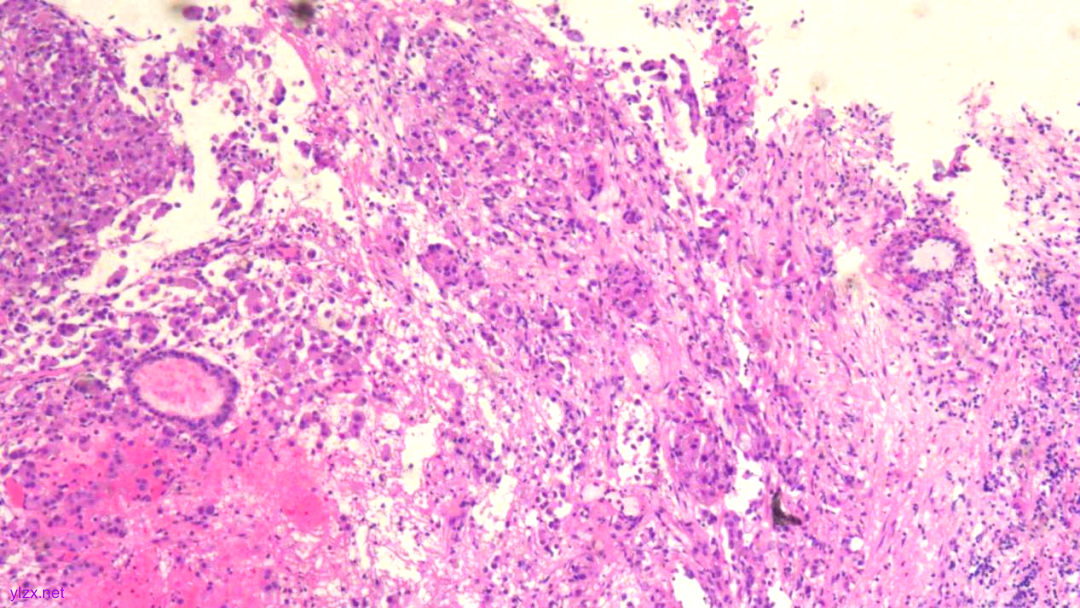

HE:

黏膜间质内见胞浆丰富,红染及粉染瘤细胞弥漫分布,部分细胞核稍偏位,核圆形,稍增大,深染,见核仁,穿插在固有腺之间,伴少量炎细胞浸润。

瘤组织穿插在固有腺之间,较弥漫,核稍增大,深染

瘤细胞稀疏排列,胞浆粉染及红染,宽阔

瘤细胞核圆形,见核仁,部分细胞核偏位,未见核分裂象

瘤细胞核仁明显